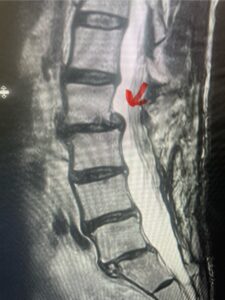

This 61-year-old female with a history of severe osteoporosis and a prior history of a laminectomy from l2-S1 with an L5-S1 instrumented fusion, presents with progressive low back pain and right lower extremity radiculopathy. MRI revealed a grade 1 L2-3 spondylolisthesis with severe stenosis mainly from severe right L2-3 facet joint hypertrophy which was compressing the right L3 descending nerve root. (Fig. 1). She had failed conservative management consisting of physical therapy and pain management with epidurals. She underwent an L1-3 revision laminectomy where we had to dissect a plane underneath the inferior aspect of the L2 lamina. We performed an instrumented fusion at L2-3 with special hydroxyapatite-coated screws to improve fixation to surrounding bone given here severe osteoporosis (Fig. 2) This worked out well and the patient had an uneventful recovery with relief of her leg pain.

Figures 1a: Sagittal and axial T2-weighted lumbar MRIs demonstrating a grade 1 L2-3 spondylolisthesis (red arrow) with severe stenosis secondary to right L2-3 facet hypertrophy (red arrow).

Fig 1b: Note the left L2-3 facet joint (blue arrow) is normal in size compared to the right (red arrow)